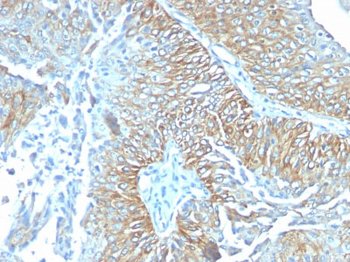

TRIM29 (Lung Squamous Cell Carcinoma Marker) Antibody

| Description | TRIM29 (Lung Squamous Cell Carcinoma Marker); Clone TRIM29/1041 (Concentrate) |

| Application notes | A431 cells. Tonsil or Squamous cell carcinoma. |